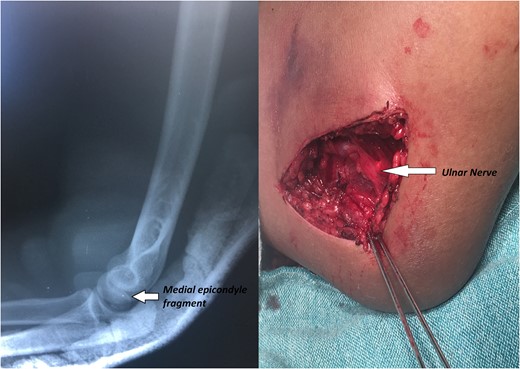

A 14-year-old male patient presented to the emergencies department complaining of intense pain in the left elbow secondary to a fall with an outstretched hand while practicing soccer. He had no significant comorbidities. At physical examination he presented with deformity located on the left elbow, he was unable to passively or actively mobilize it, he reported paresthesias and diminished sensation located on the fifth and fourth digit. X-rays showed a dislocation on the left elbow and an avulsive fracture of the medial epicondyle of the distal humerus (Fig. 1). He was taken to the operating room where a closed manipulation was performed; however the reduction was not achieved due to the interposition of the fractured medial epicondyle. A medial approach to the elbow was performed; intra-operative findings included rupture of the medial capsule and intra-articular interposition of the fragment of the medial epicondyle with a posterolateral dislocation of the elbow, the ulnar nerve showed compressive injuries at the site of the fracture (Fig. 2). Extraction and fixation of the interposed intra-articular fragment was performed followed by elbow reduction and a medial capsule repair, without ulnar nerve transposition (Fig. 3). The patient was left with a posterior splint for a month. After a 3 month follow-up, he has recovered full range of motion of the elbow with recovery of strength and sensation over the distribution of the ulnar nerve.

X-rays showing the result of the first attempt of closed manipulation and open reduction.

We decided to fix the fragment with k-wires taking in account of the frequent complications of the use of screws, such as the need of hardware removal in almost 20% of patients of the larger case series revised, however the use of screws has been recommended, especially in cases with older patients, mainly to gain stability and allow early range of motion [3, 7–9].